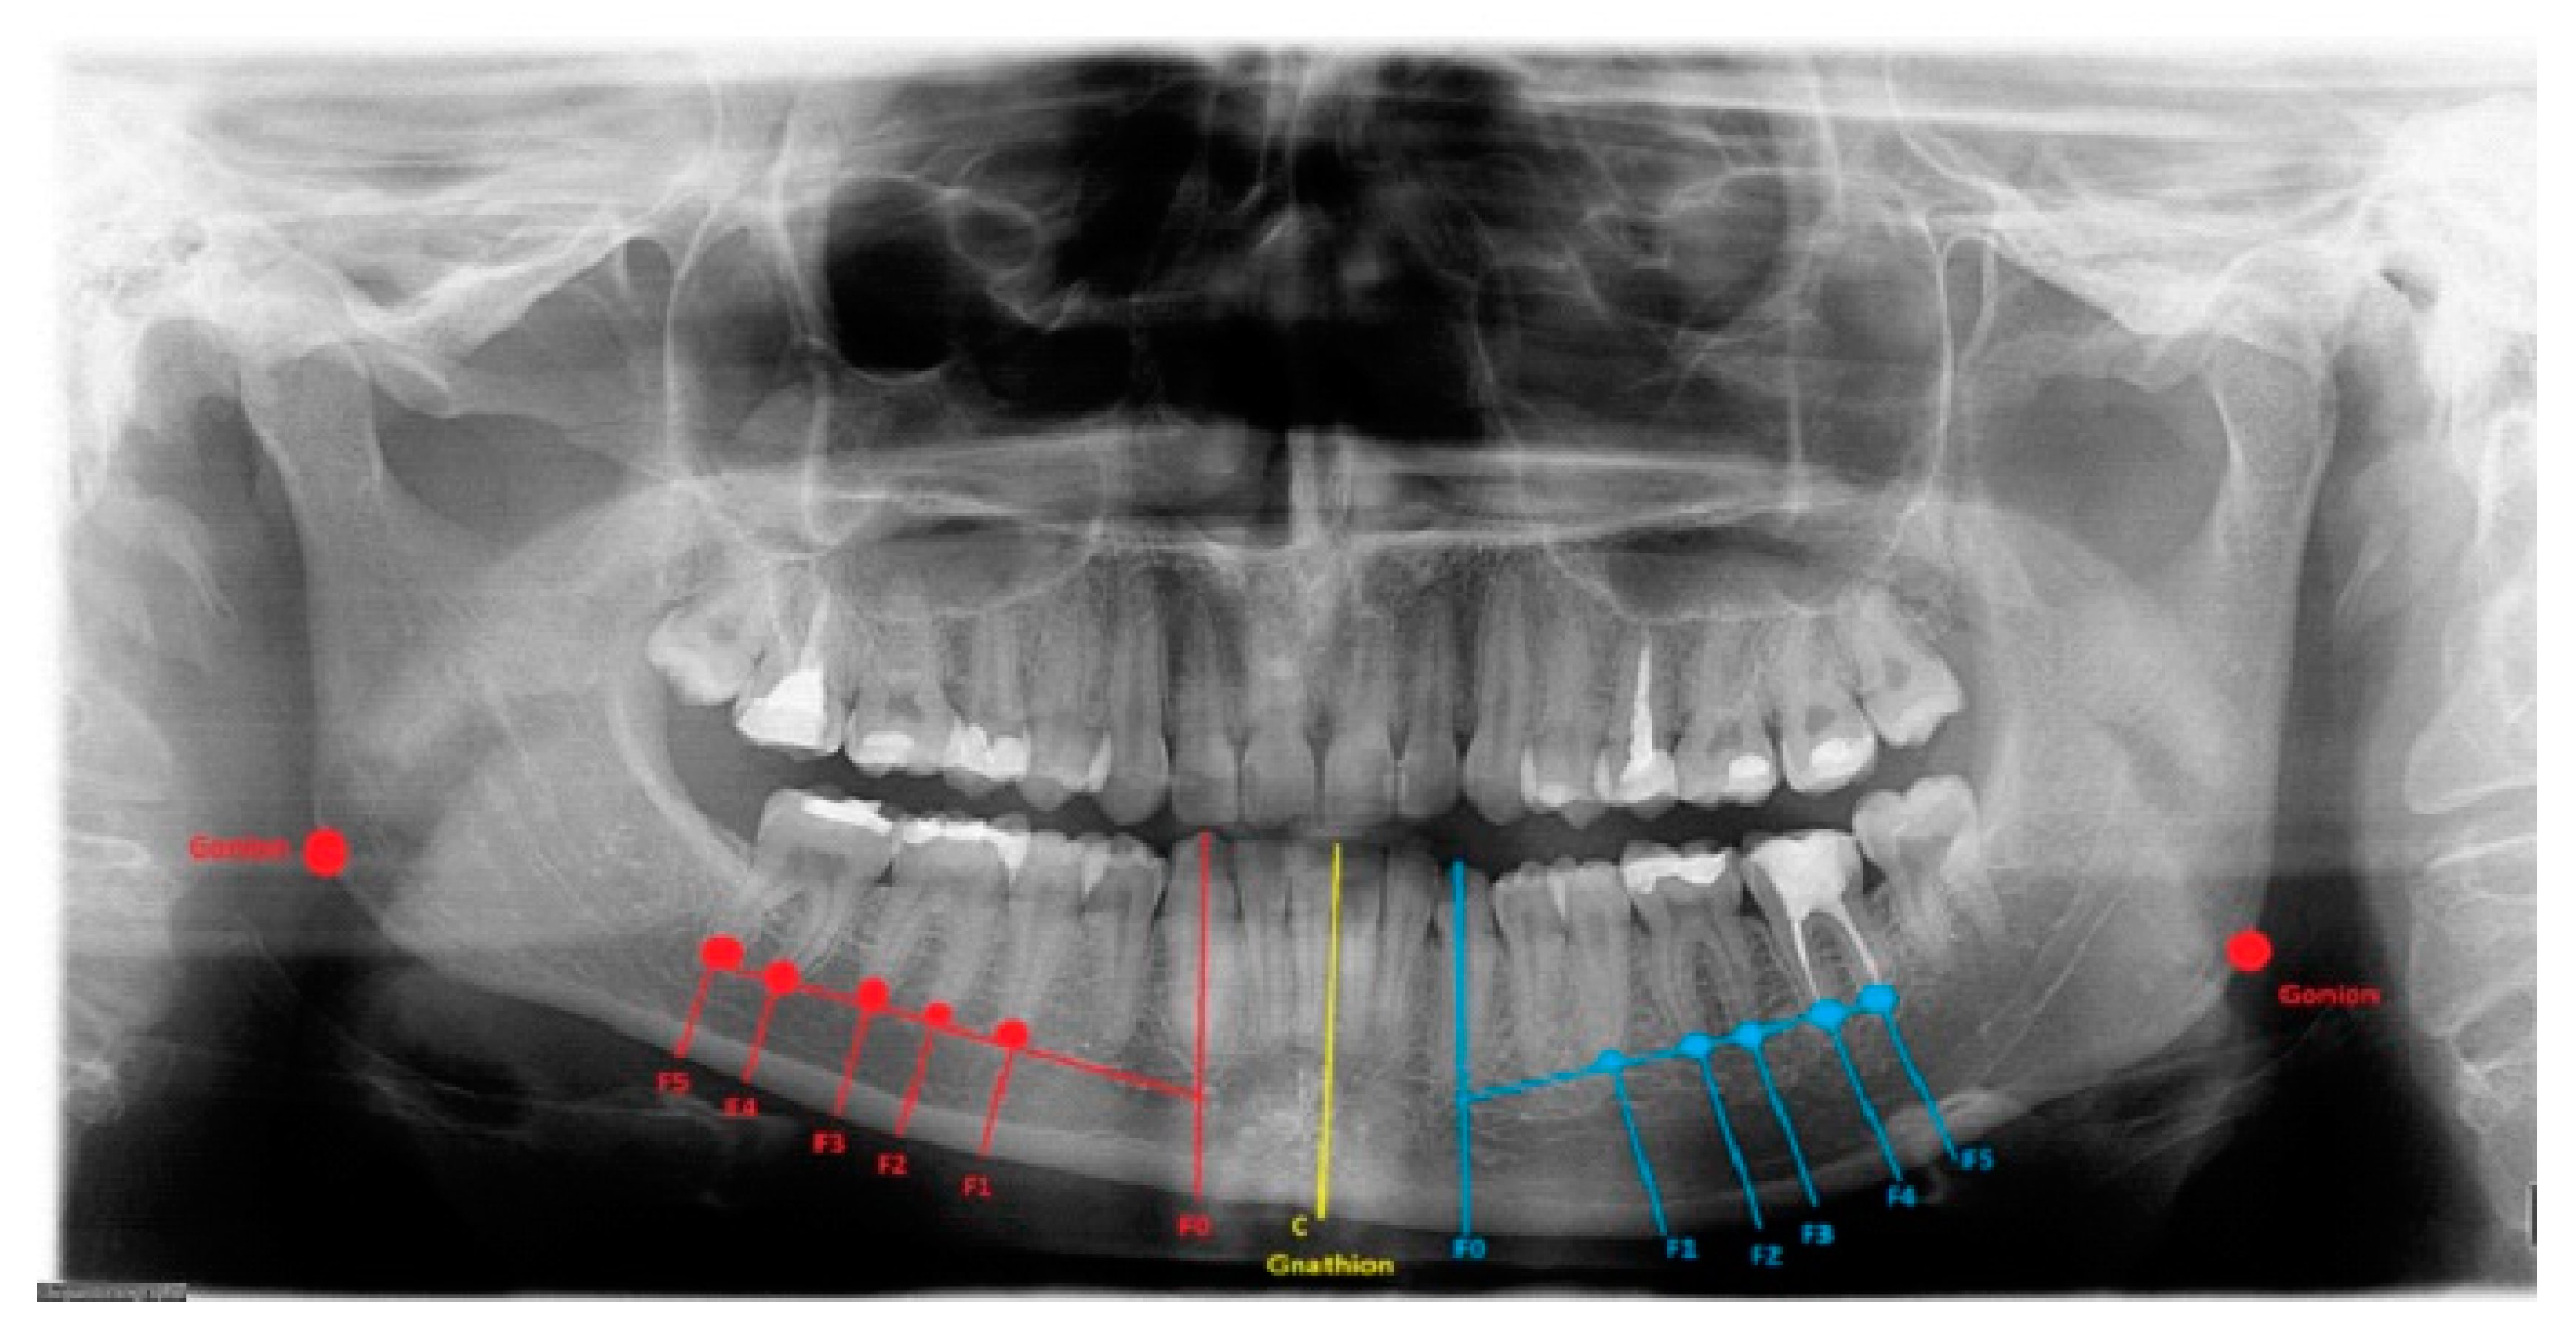

Figure 1.

Mild form of condylar hyperplasia. Red and blue lines marked F0–F5 help to visualize the distances between the tooth apex, the mandibular canal, and the mandibular base. Gonion and gnathion landmarks help to define right/left bone proportions and lengths. The yellow midline always marks the teeth and the mandibular midline. The degree of bone overgrowth and mandible angle shape and volume can be easily estimated.

Secondly, the lower border of the mandible was outlined, and a vertical line from the tip of the canine, premolars, and molars was drawn perpendicular to the outlined marginal baseline. The collected radiological (panoramic) and tomographic (CT/LDCT) data were converted and archived. The horizontal volume of the bone from the tip of the roots toward the mandibular base was measured (Figure 1). Additional landmarks were set on the course of the mandibular canal to determine the distances between the roots, the mandibular base, and the mandibular canal itself.

3.1. Mandibular Canal

The distance between the mandibular canal and the inferior mandibular border—at least 5 mm of vertical bone overgrowth (Table 2)—could indicate the usage of marginectomy. The MIB cut (approx. 5–10 mm) is performed just under the inferior border of the mandibular canal. The degree of bone excised is measured by IM and ARP (Figure 1). When the vertical bone height is limited (<5 mm) due to a low-set mandibular canal, approach three should be used. On the other hand, marginectomy or marginectomy-swing could be performed if there is ≥7 mm of vertical bone overgrowth, and the mandibular canal is positioned ≥5 mm from the MIB. While a single cut might damage the mandibular canal, altering it with two, three, or more cuts can reduce this damage due to the curved cut line. An indication for this approach is a low-set mandibular canal with irregular placement along with the MIB, according to index measurements of teeth apices F0–F5 (Figure 1; Table 1 and Table 2). The suggested measurements in preoperative radiographs on the degree of bone overgrowth influence the used surgical approaches in the authors’ proposed perspective.

The length between Go-Gn/Go-Gn and the vertical bone volume relation decreases the bone height on the opposite healthy side—the critical point of this technique is the distance between the Go-Go/Go-Gn position and the value of the F0-C bone index. In this case, approach 1C can be used with or without corrective angulotomy/anguloplasty, which reduces the angled volume on the affected side in vertical and horizontal dimensions. If both Go (Right) and Go (Left) are situated on the same horizontal line, no major surgery should be planned, unless performing a condylectomy might relocate the Go point on the affected side to a higher position afterward. Therefore, careful planning in the horizontal plane and the F5: Go measurement can help estimate whether any additional mandibular angle surgery should be planned (Figure 1 and Figure 2; Table 1). This was used in some of the authors’ cases where there was no maxillary bite-plane deviation, and no chin bone asymmetry was present.

3.3. Chin Symmetry

The chin area position in IM and ARP (Figure 1)—severe chin area asymmetry—could be treated with the surgical approach suggested by Ferguson, while smaller ones could be successfully treated conservatively by drilling and bone reshaping or with other proposed methods of marginectomy. IM is used when the distance between C and F0 is equal (1:1); when C < F0 in both the vertical and horizontal dimensions, then a leveling and/or corrective genioplasty is used by the authors (Figure 1; Table 2). After the inferior dental neurovascular bundle is wholly free and retracted, bone correction and reshaping of the new inferior alveolar nerve canal is performed. Instead of a leveling genioplasty, the remnants of the overgrowth are smoothed with surgical drills. In the authors’ system, the primary key factor is total chin correction, which is necessary in cases of severe overgrowth; when F0 > C and Go-Gn>, there is >7 mm of vertical bone overgrowth, and the mandibular canal is positioned <5 mm from the MIB. The presented measurements are novel and not used in any previous reports and should be considered an additional tool for surgery planning.

The authors indicate that a modification of the classic, horizontally performed, one-cut mandibular marginectomy—and changes consisting of two, three, or more cuts—can be used to reshape the overgrown mandibular base on its hyperplastic side. Distances measured with ARP: IM help to indicate the degree of bone resection (Table 2). It could also be used to reshape the mandibular angle on the hyperplastic side of the mandible or can be used with simultaneously performed anguloplasty and/or angulotomy—if the mandibular angle is enlarged and more square-shaped. Furthermore, this same approach can be used to avoid damage to the inferior alveolar nerve in its canal with the multiple horizontal cuts, while a single one could damage the nerve [3,4,5,6]. The tooth apices: MIB index values help in the possibility of lower border modeling estimation (Figure 1).

The authors conclude that a very severe mandibular overgrowth with increased chin involvement should be a mandatory indication for the classic Ferguson approach with a surgical reduction in the mandibular angle on the affected side [7,13]. The main reason for this is the increased distance and height of the F0:F1 and F0:C:F0 values in this study (Figure 1). The authors fully agree with Ferguson’s approach, which is confirmed in the author’s measurements based on the suggested ARP: IM values and the distances between reference points in the presented study radiographs. Two different cases of one-sided mandibular overgrowths in hemimandibular hyperplasia are drawn and explained in Figure 2.